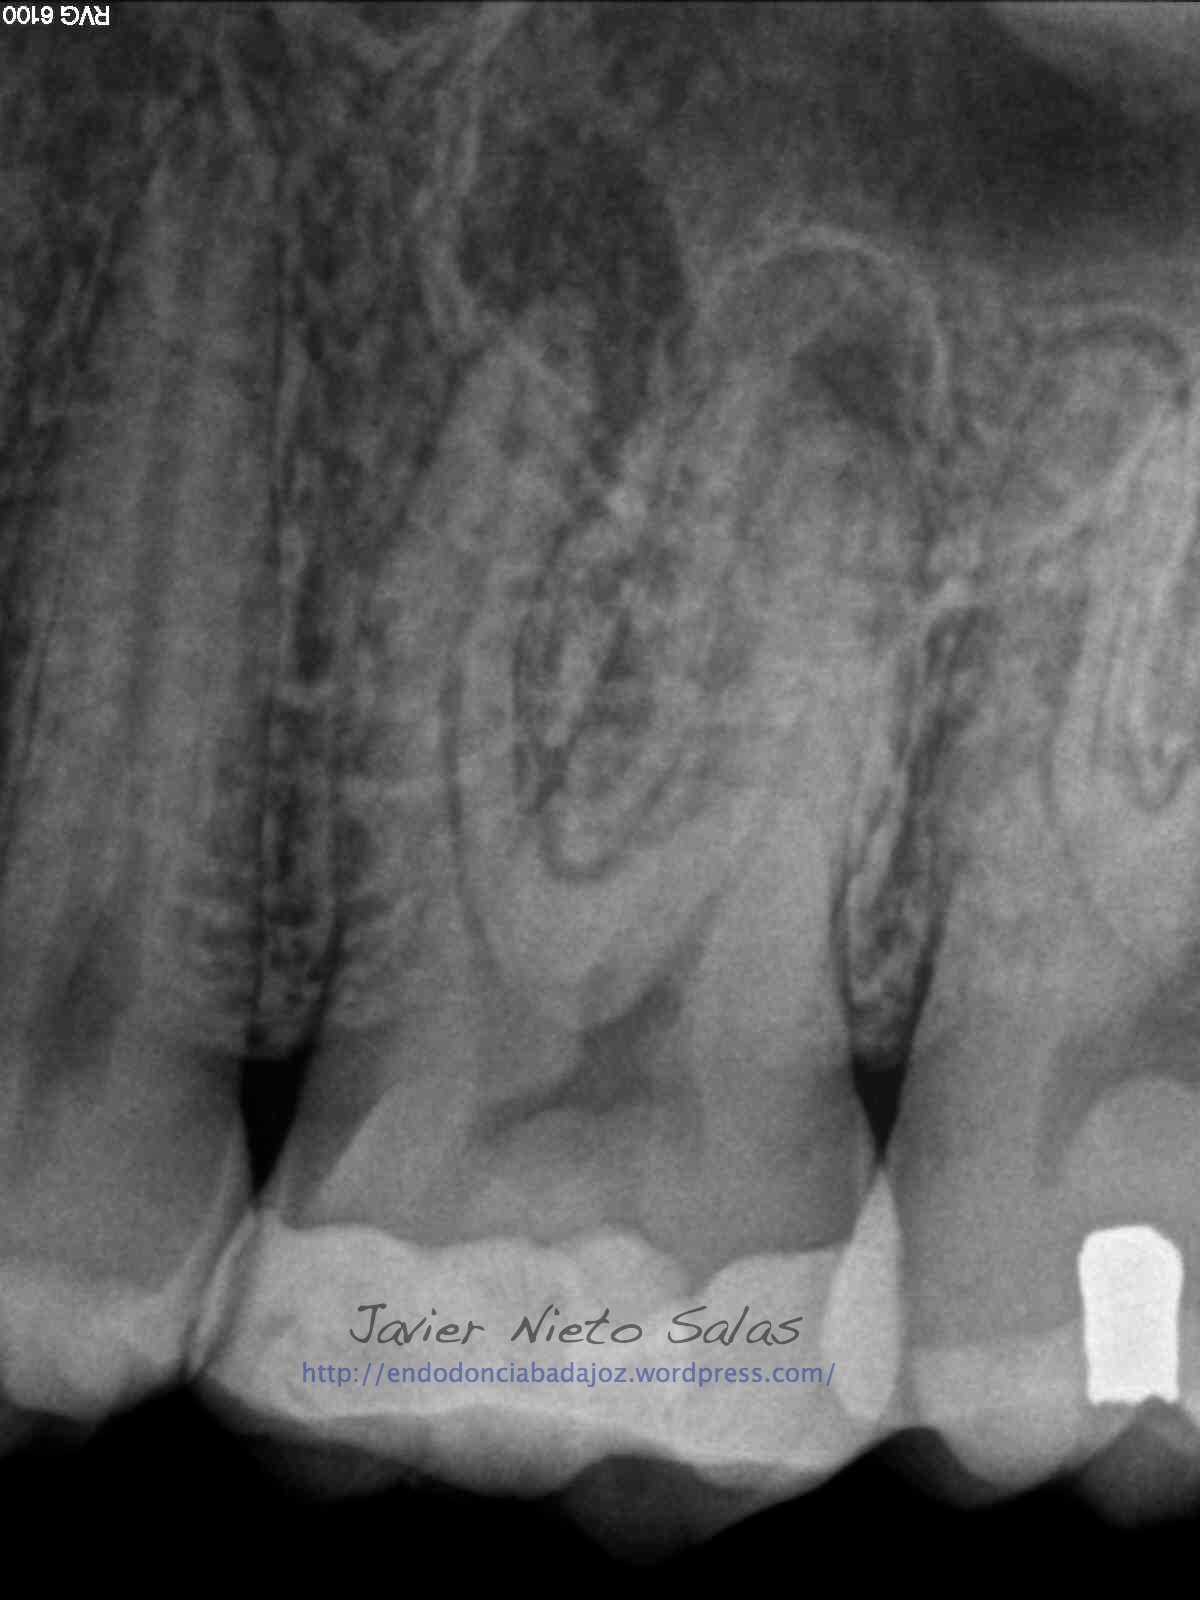

Nos llega un paciente con una PERIODONTITIS APICAL CRÓNICA, le realizamos el tratamiento de conductos, instrumentaríamos con sistema M-Two y obturaríamos con la técnica de Ola contínua de Buchanan y un backfilling con la pistola Obtura II. Se utilizó Microscopio Zeiss con luz xenón, y se han tomado las fotografías con una cámara Sony.

Como podemos ver, en las Rx finales, no afecta el ser conservadores con la estructura dentaria en el tratamiento y resultado final.